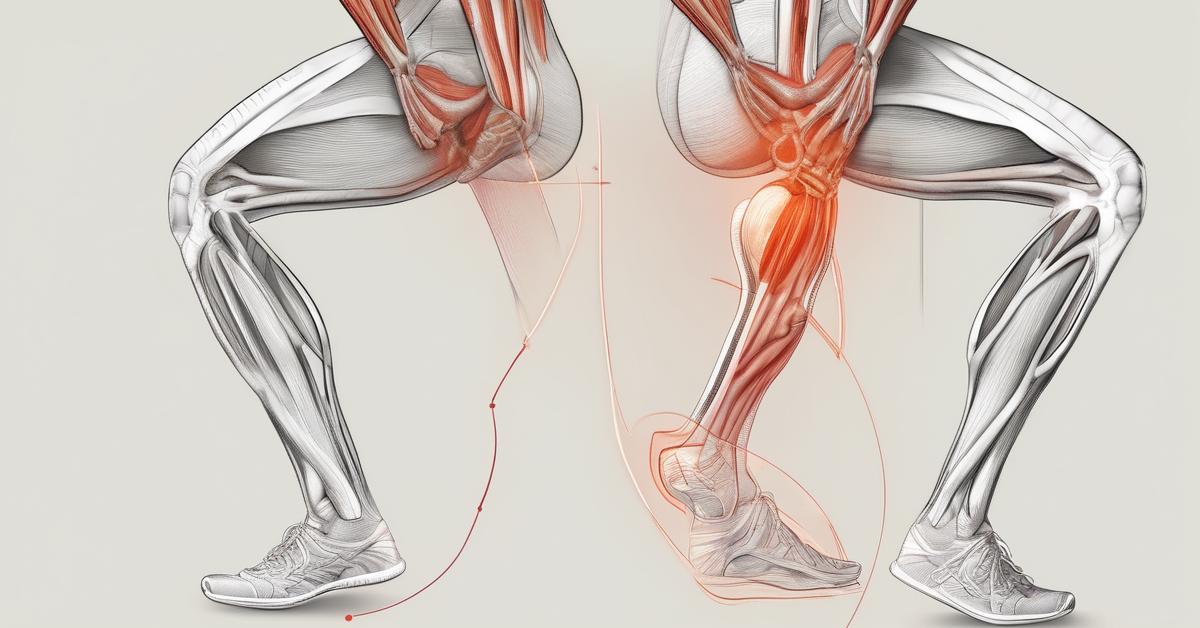

- Ćwiczenia na łydki w domu: 3 proste ćwiczenia na mięśnie łydek